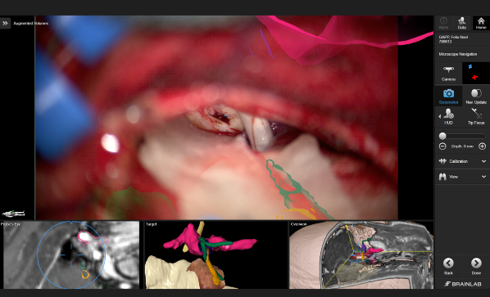

Asymptomatische Cavernome können nur beobachtet werden. Symptomatische Cavernome sind operativ zu entfernen. Die Blutungsrate bewegt sich zw. 0,25 und 2,3% pro Patient und Jahr. Nach stattgehabter erster Blutung beträgt die Rate 4,5% für eine Reblutung pro Jahr. Der entscheidende Faktor ist die Lokalisation des Cavernoms. Ist das Cavernom im Hirnstamm oder den Basalganglien lokalisiert, beträgt die erneute Blutungsrate 10,6 % pro Jahr. Daraus ergibt sich, dass diese Cavernome, wenn sie geblutet haben, operativ entfernt werden sollten. Durch die moderne Mikrochirurgie mit den Hilfsmitteln der Neuronavigation, Ultraschall und dem intraoperativen elektrophysiologischen Monitoring lassen sich Cavernome selbst in solch kritischen Hirnarealen schonend entfernen. Die radiochirurgische Behandlung ist unserer Ansicht nach keine sinnvolle Alternative.

Die Abbildung zeigt die Planung zur Entfernung eines Cavernoms des Hirnstamms mit Hilfe der Augmented Reality und die intraoperative Darstellung. Das Cavernom konnte komplett entfernt. Die durch die Blutung entstandenen neurologischen Ausfälle haben sich nach der Operation komplett zurückgebildet.